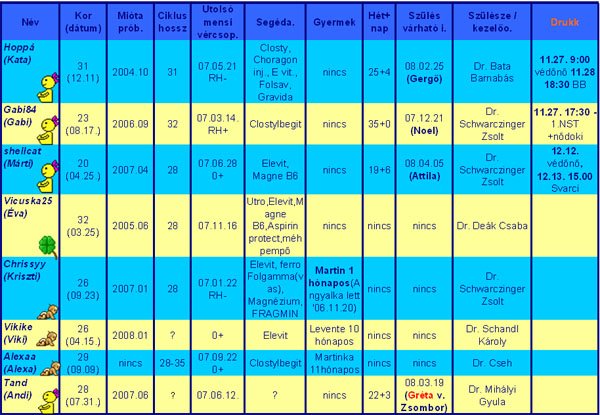

milyen lett az EKG eredmény? Ezt az sztk-ban csinálják?? Hát, nem semmi a doki beosztásod, lassan tényleg új tábla kell, hogy ezek beleférjenek